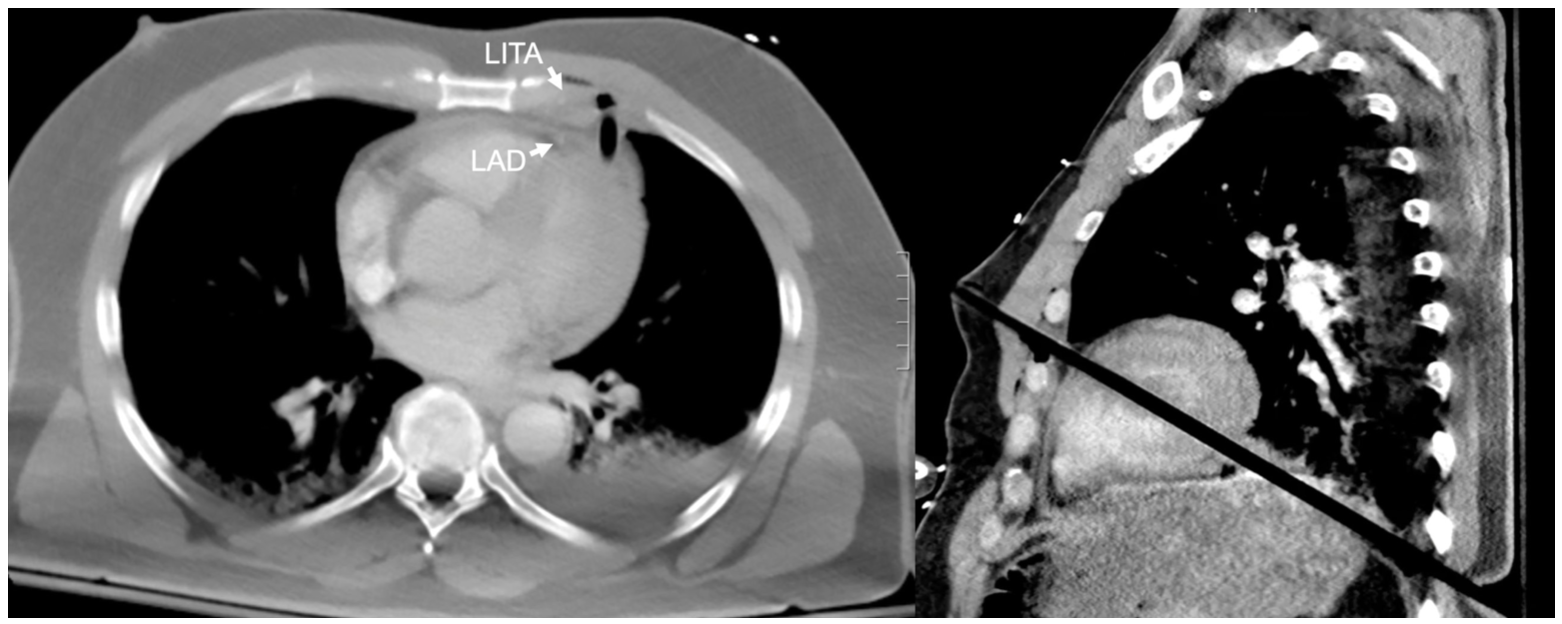

We initiated cardiopulmonary bypass via the femoral artery and vein prior to median sternotomy. The anterior part of the arrow between the pericardium and the anterior LV wall was separated (Figure 3B). Next, we separated the posterior part of the arrow between the posterior LV wall and pericardium (Figure 3C). We confirmed that the arrow was between the left anterior descending artery and the diagonal branch in the anterior LV as well as between the posterior descending artery (Figure 3H) and posterior lateral branch (Figure 3F). Following extraction, the defects were closed with felt-reinforced horizontal mattress stitches and over-and-over stitches as in the linear LV closure. Of note, there were fibrin clots surrounding the arrow (Figure 3E). We discontinued cardiopulmonary bypass smoothly and achieved excellent hemostasis without segmental abnormalities in LV motion and valve malfunction. The patient was extubated several hours after the operation and had an uneventful postoperative recovery. Postoperative follow-up revealed that he was incredibly grateful to be alive and thankful to the multidisciplinary team that saved his life.